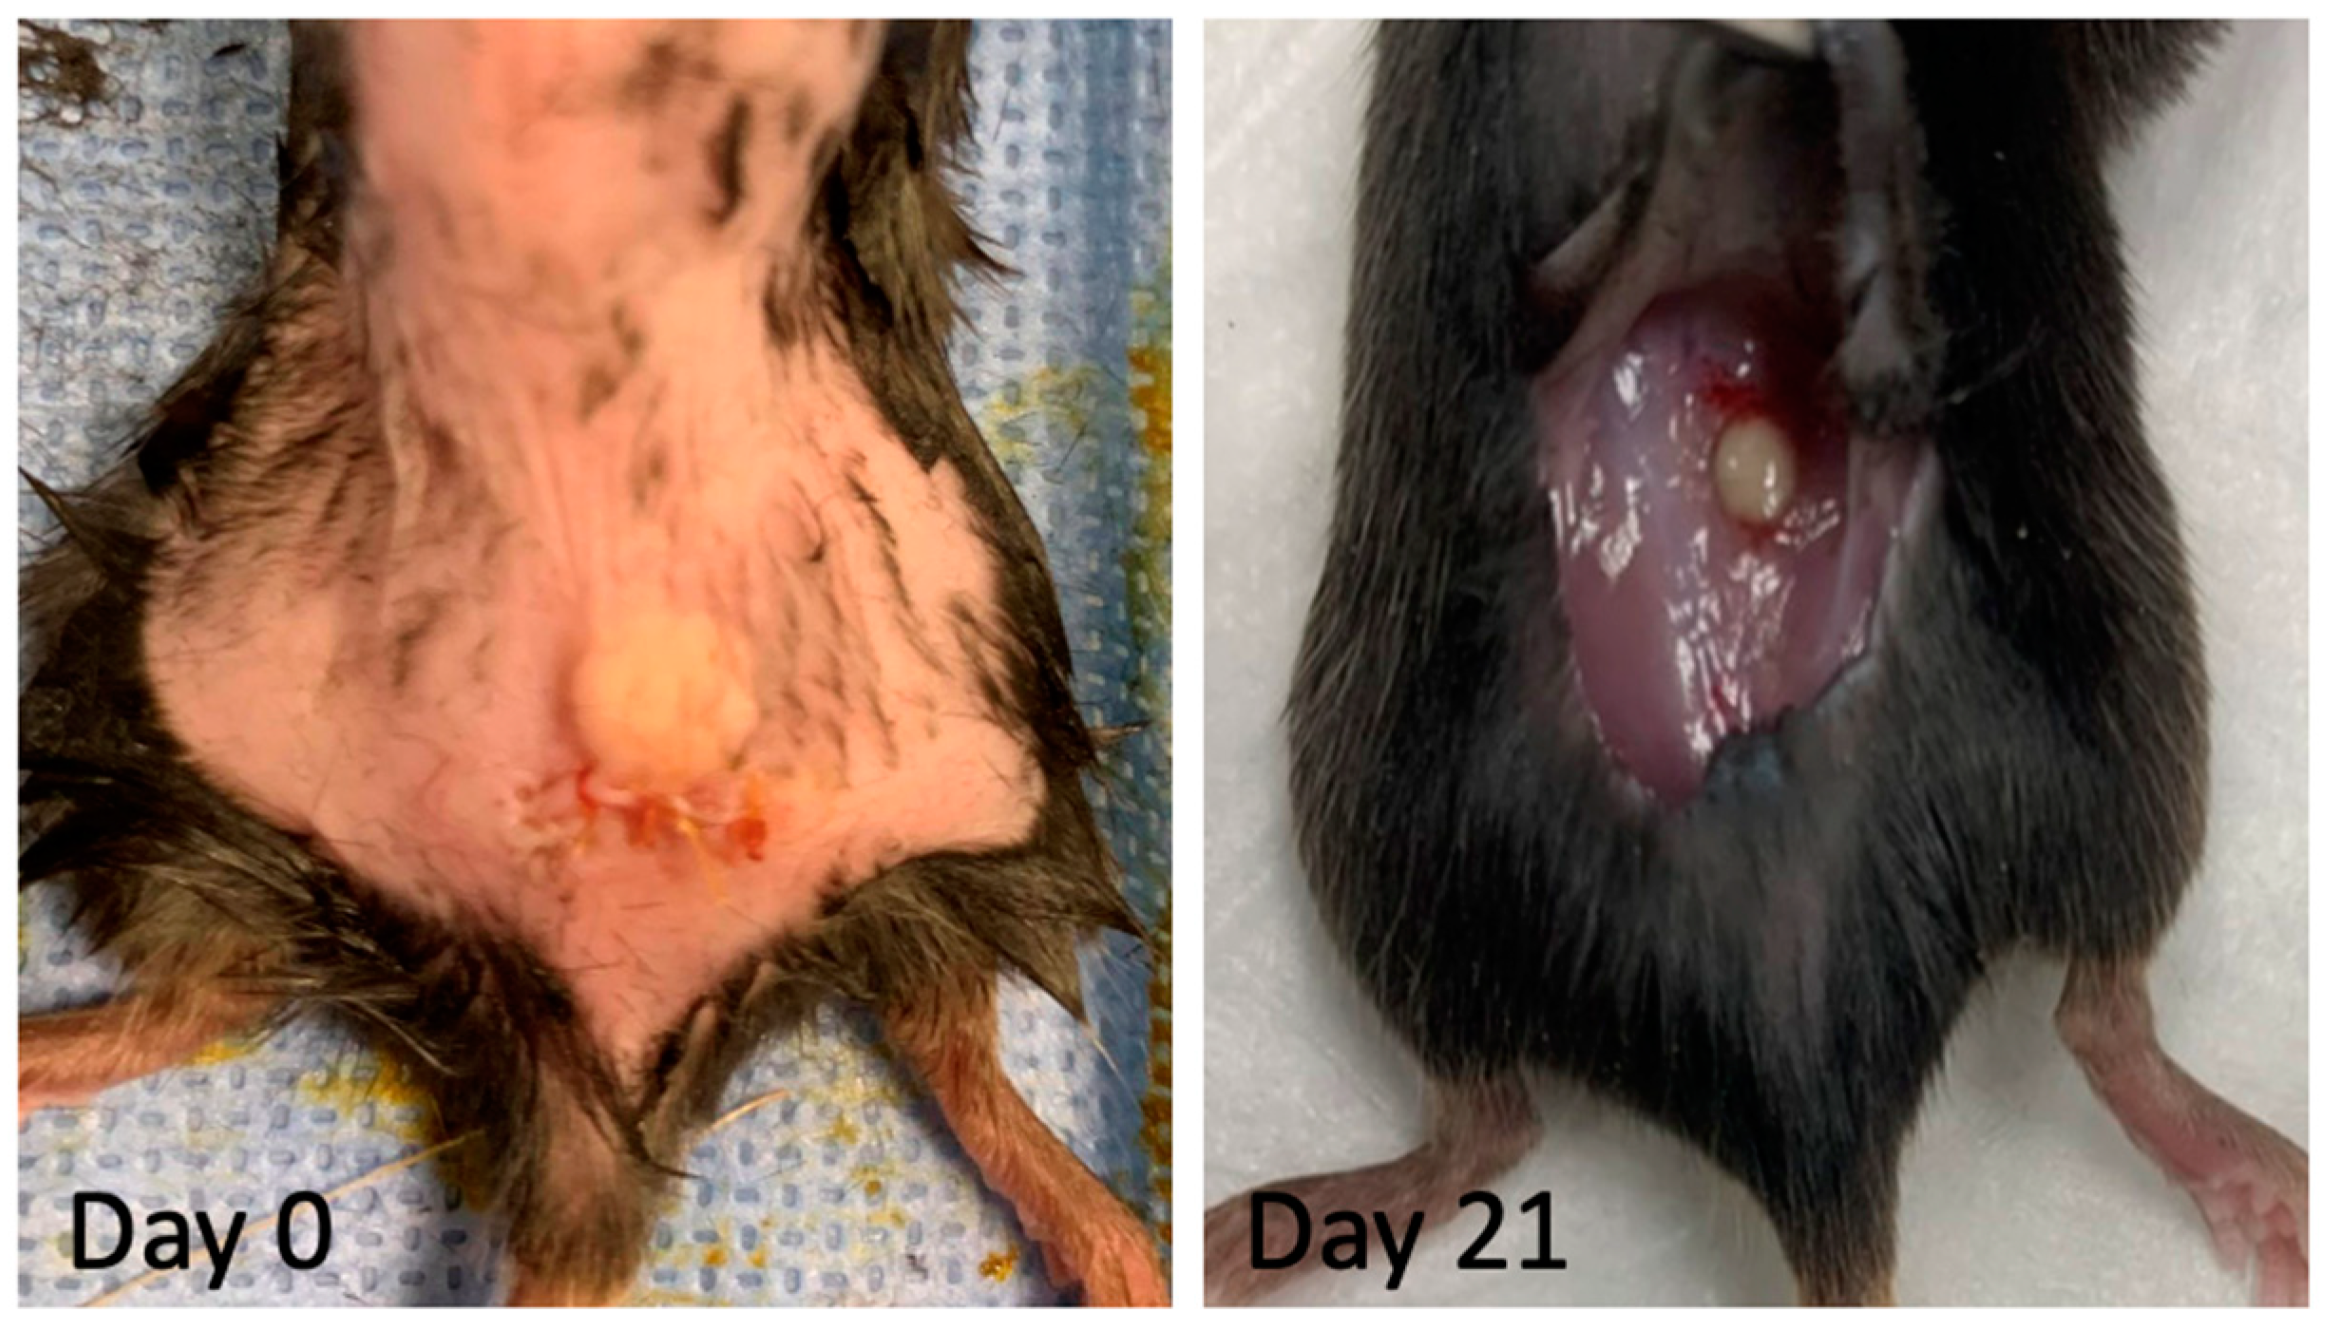

2.10. Implantation of Decellularized Grafts for Immunological Evaluation

3.4. In Vitro and In Vivo Biocompatibility of Decellularized Facial Grafts